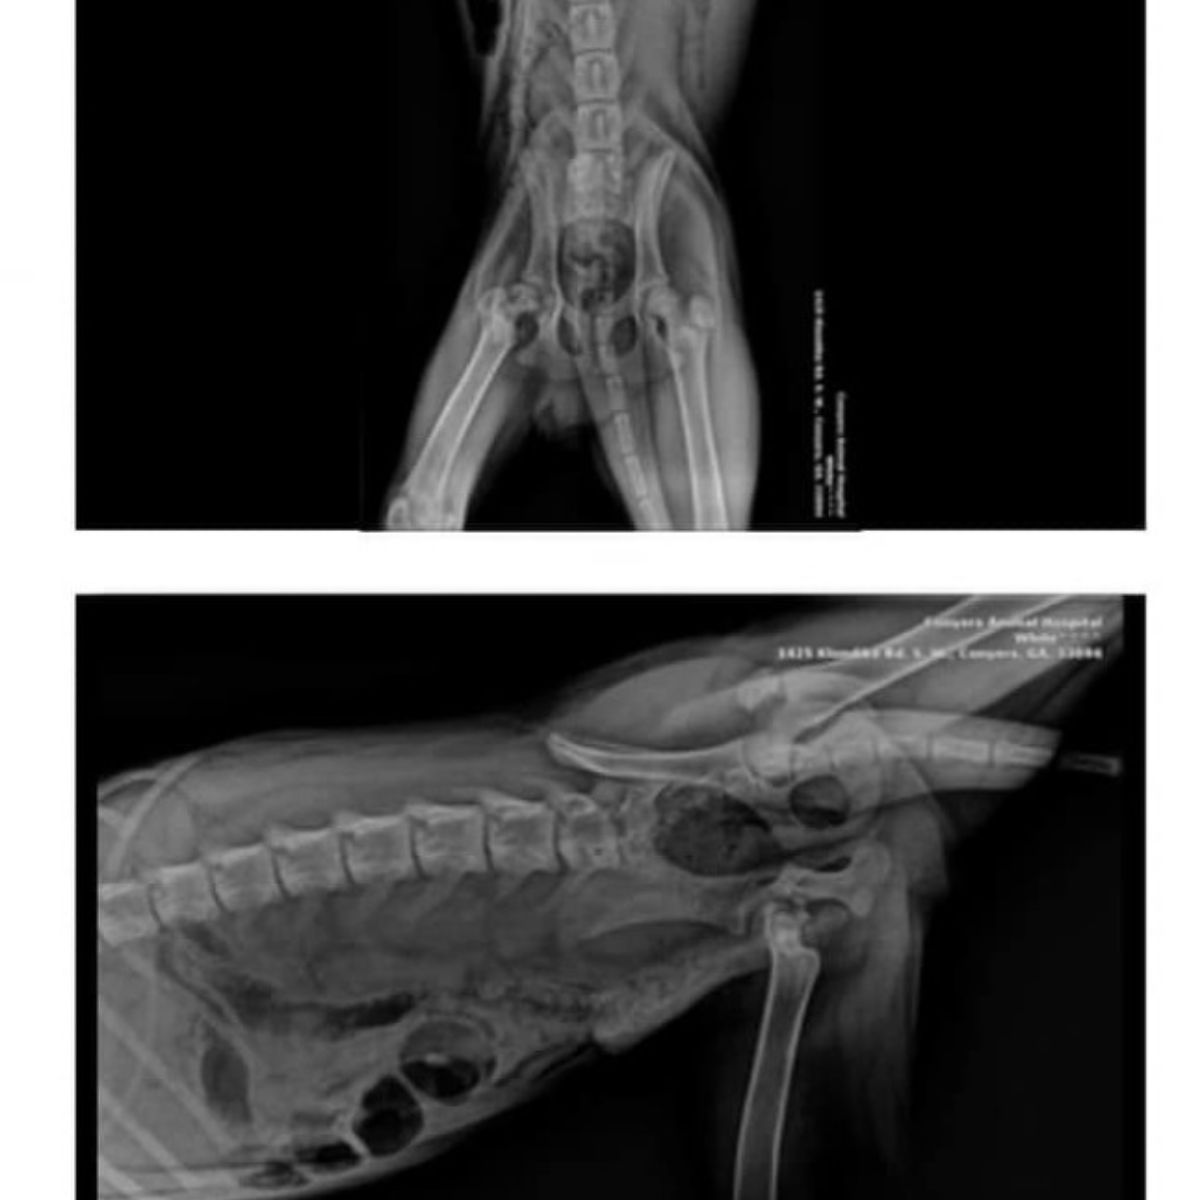

Переходець помітив цуценя і повідомив місцеве притулок. Оглянувши Ханка, волонтери виявили: одна з лап серйозно пошкоджена — перелом, що, за висновком ветеринарів, тривав щонайменше два тижні. Біль і виснаження робили собаку майже нерухомим. Початкова рекомендація лікарів була жорсткою — евтаназія, щоб припинити страждання. Команда порятунку відмовилася прийняти таке рішення і вирішила боротися за життя песика.

- Діагностика: давній перелом, біль і виснаження;